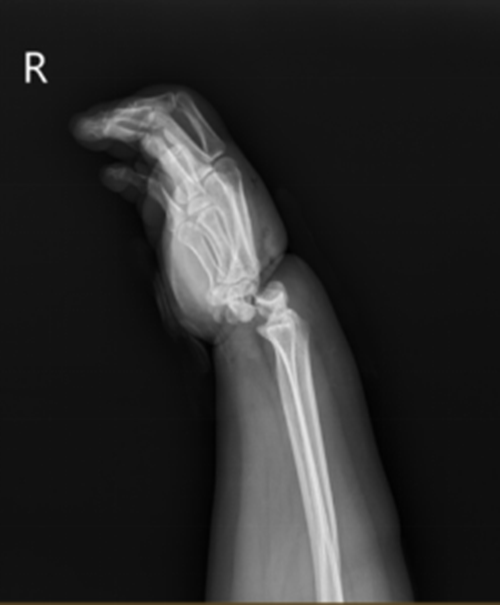

Khi Tiểu Mỹ được xe cấp cứu đưa đến Bệnh viện số 2 Ninh Ba, khớp cổ tay của cô đã bị gãy và trật hoàn toàn, bác sĩ xác định lưu thông máu kém. Sau khi tham khảo ý kiến của bác sĩ phẫu thuật vi phẫu tay, xác định rằng khớp cổ tay cũng như nguồn cung cấp máu động mạch và tĩnh mạch xa của Tiểu Mỹ có thể đã bị cắt đứt và cần phải ghép lại cổ tay bị đứt ngay lập tức.

"Lần đầu tiên tôi gặp bệnh nhân này, bàn tay phải của cô ấy sưng tấy rất nặng, cổ tay bị biến dạng nghiêm trọng, vùng da bị dây thừng siết cổ bị hoại tử và toàn bộ lòng bàn tay chuyển sang màu tím do thiếu máu cục bộ", bác sĩ cho biết sau khi khám.

Tuy nhiên, đã 3 giờ trôi qua kể từ lúc Tiểu Mỹ bị thương đến khi tới viện, huyết khối đã hình thành trong các mao mạch ở lòng bàn tay, thời gian trì hoãn càng lâu thì khả năng hoại tử lòng bàn tay do thiếu máu cục bộ càng lớn, phải phẫu thuật ngay lập tức. Phải mất hơn 4 giờ đồng hồ mới cứu được bàn tay phải của Tiểu Mỹ và xây dựng lại nguồn cung cấp máu cũng như chức năng cho nó.